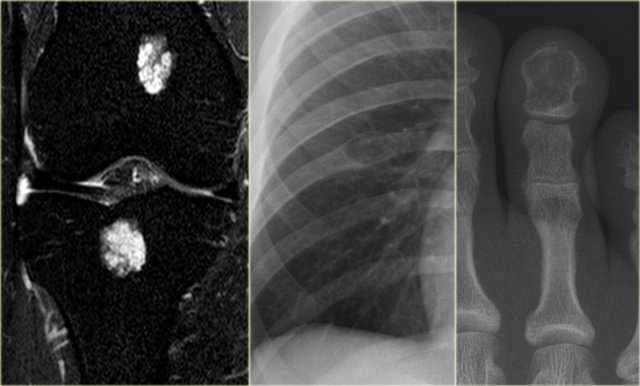

- left

Fat suppressed coronal PD-image of the knee. Typical enchondromas in the femur and tibia as seen frequently as coincidental finding in MR-examinations. - middle

Well-defined lytic lesion in the rib with cortical thinning. - right

Well-defined lytic lesion with a sclerotic margin and without calcifications in the end phalanx.